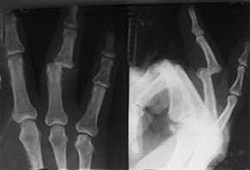

При множественных вывихах с значительными смещениями и сложных дивергирующих вывихах возможность закрытого вправления сомнительна, особенно при наличии сопутствующих переломов пястных костей, что требует открытых вправлений (рис. 72).

Ладонные вывихи чаще, чем тыльные, не удается вправить закрыто. Даже среди сравнительно легко устранимых вывихов V пястной кости ее ладонно-лучевые смещения обычно требуют оперативного вмешательства из-за препятствий со стороны крючковидной кости. Вывихи V пястной кости являются неустойчивыми, и для их удержания необходима иммобилизация с сгибанием проксимальной фаланги до 90° и легким разгибанием кисти с супинацией для снятия напряжения межкостных мышц и локтевого разгибателя [Berg Е., Murphy D., 1986]. Другие виды вывихов также могут быть нестабильными, что проявляется сразу после вправления или позже. Иммобилизация в течение 6 недель с фиксированными пальцами может привести к их тугоподвижности. Поэтому, помимо ретроградной стабилизации спицами запястно-пястных суставов при неустойчивых и невправимых вывихах, целесообразно производить аналогичную чрескожную стабилизацию спицами даже при вправленных устойчивых вывихах. Это позволяет начать раннюю мобилизацию пястно-фаланговых суставов, в которых чаще всего развивается тугоподвижность, и сократить период иммобилизации в гипсовой повязке [SgrabyG., Sabetta Т., 1968; Hazlett J., 1968; Sedel L, 1975].